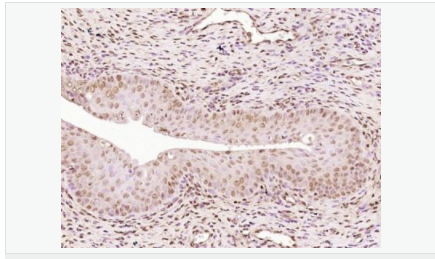

| 英文名稱 | Progesterone Receptor |

| 中文名稱 | 孕激素受體抗體 |

| 產(chǎn)品應用 | WB=1:500-2000 IHC-P=1:100-500 IHC-F=1:100-500 Flow-Cyt=1ug/Test ICC=1:100-500 IF=1:100-500 (石蠟切片需做抗原修復) not yet tested in other applications. optimal dilutions/concentrations should be determined by the end user. |

| 細胞定位 | 細胞核 細胞漿 |